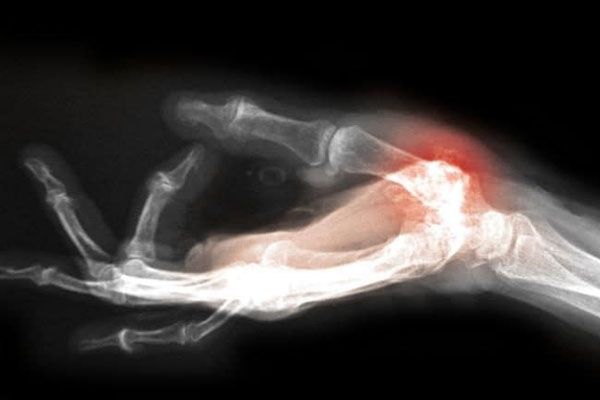

لندن: اكتشف باحثون في الولايات المتحدة أن طفرة وراثية تزيد خطر الاصابة بالتهاب المفاصل حدثت في العصر الجليدي لحماية أسلافنا من قضمة الصقيع.

ويحمل نحو نصف الاوروبيين نوعاً متحولا من الجين "جي دي اف 5" الذي يضاعف مرتين تقريباً خطر نشوء آلام في المفاصل ويقصّر طول القامة نحو سنتم.

ولأن التهاب المفاصل لا يظهر عادة إلا بعد السن التناسلي فانه لم يكن عائقاً امام تكوين عائلة وبهذه الطريقة انتقلت الطفرة من جيل الى آخر ، كما يؤكد العلماء.